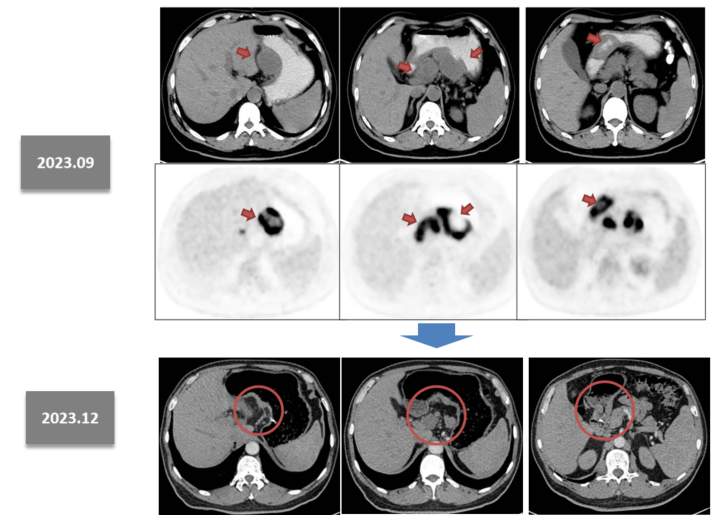

术后于2024年1月至5月,继续接受了5个周期的斯鲁利单抗联合SOX方案辅助治疗。

维持治疗

2024年6月至今 ,现单免维持治疗23个周期,目前仍在继续单免维持治疗。

930.9.png

图3 2024年1月、2025年3月复查结果

患者目前生存状态良好,肿瘤标志物水平在治疗后持续下降并维持在正常范围,未见肿瘤复发或转移迹象。